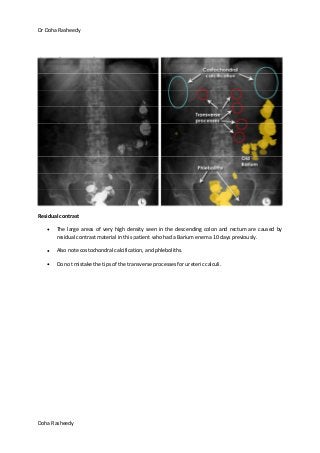

Residual contrast

The large areas of very high density seen in the descending colon and rectum are caused by

residual contrast material in this patient who had a Barium enema 10 days previously.

Also note costochondral calcification, and phleboliths.

Do not mistake the tips of the transverse processes for ureteric calculi.